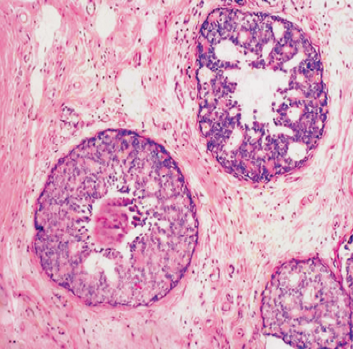

(2)小叶原位癌(lobular carcinoma in situ) 小叶原位癌发生于乳腺小叶的末梢导管和腺泡。扩张的乳腺小叶末梢导管和腺泡内充满呈实体排列的癌细胞,癌细胞体积较导管内癌的癌细胞小,大小形状较为一致,核圆形或卵圆形,核分裂像罕见。增生的癌细胞未突破基底膜。一般无癌细胞坏死,亦无间质的炎症反应和纤维组织增生。

约30%的小叶原位癌累及双侧乳腺,常为多中心性,因肿块小,临床上一般扪不到明显肿块,不易和乳腺小叶增生区别。发展为浸润性癌的几率和导管内原位癌相似。